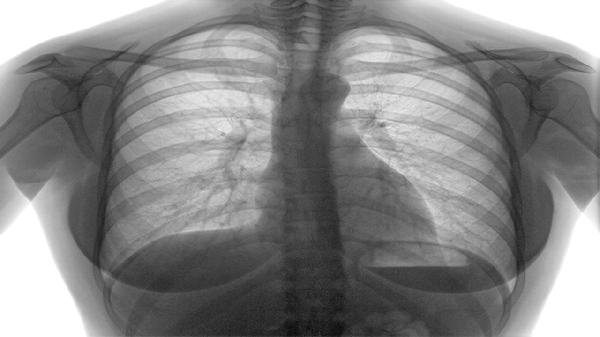

慢阻肺治疗药物喷剂主要有布地奈德福莫特罗粉吸入剂、沙美特罗替卡松粉吸入剂、噻托溴铵粉吸入剂、异丙托溴铵气雾剂、富马酸福莫特罗粉吸入剂等。慢阻肺是一种以持续气流受限为特征的慢性气道炎症性疾病,患者需遵医嘱长期规范使用药物控制症状。